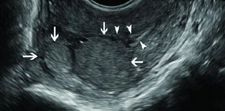

Tanı YöntemleriKafa içindeki lezyonların tanısı, genellikle hem klinik muayene hem de görüntüleme yöntemleri ile konulur. Kullanılan başlıca yöntemler şunlardır: